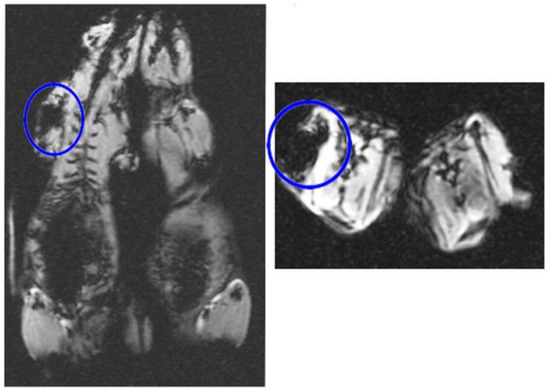

3.5. In Vivo MRI